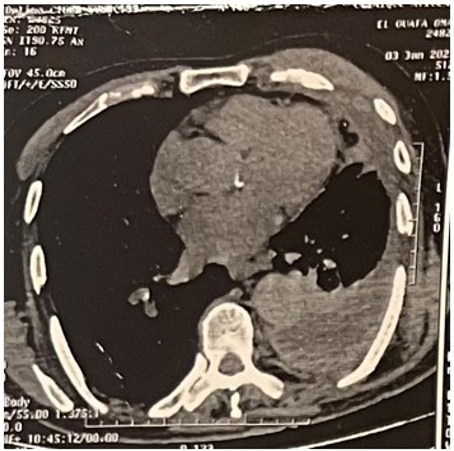

Chest CT showed hypertrophy and densification of the left mammary gland (24 mm), with a soft tissue mass measuring 76.7 × 32.2 × 62 mm projecting over the 4th rib, which appeared slightly demineralized near the chondrocostal junction. Mediastinal fat infiltration and centimeter- to subcentimeter-sized lymph nodes were identified, the largest in Barety’s space. A thick pleural effusion and a 5 mm left mammary chain lymph node were noted. The pleura appeared thickened (8.1 mm), slightly hyperdense. Lung window analysis showed peribronchial micronodules in the upper lobe and apical segment of the right lung, with bilateral interstitial involvement and additional micronodules in the left lung (Figure 3). A tissue biopsy was performed on fatty and fibrous tissue. Absence of normal or pathological breast parenchyma. the GeneXpert and the search for acid-fast bacilli (AFB) performed on the ulceration swab were negative.

Figure 3: Axial CT scan showing a left breast mass with a maximum diameter of 76.7 mm.